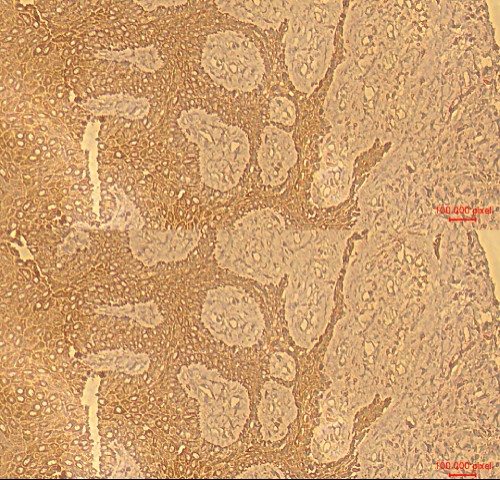

The Central Research Laboratory, Department of Research, Meenakshi Academy of Higher Education and Research (MAHER), successfully conducted a Three-Day Hands-on Workshop on Immunofluorescence and Immunohistochemistry from 23rd to 25rd July 2025 at No.12, Vembuliamman Koil Street, West K.K. Nagar, Chennai – 600 078.

The workshop was organized under the guidance of Dr. D. Nalini, Organizing Secretary, and featured dedicated hands-on sessions in Immunofluorescence on Day 1, followed by advanced training in Immunohistochemistry on Day 2 and Day 3. Participants gained in-depth practical knowledge and exposure to modern laboratory techniques, making it a highly interactive and impactful learning experience.